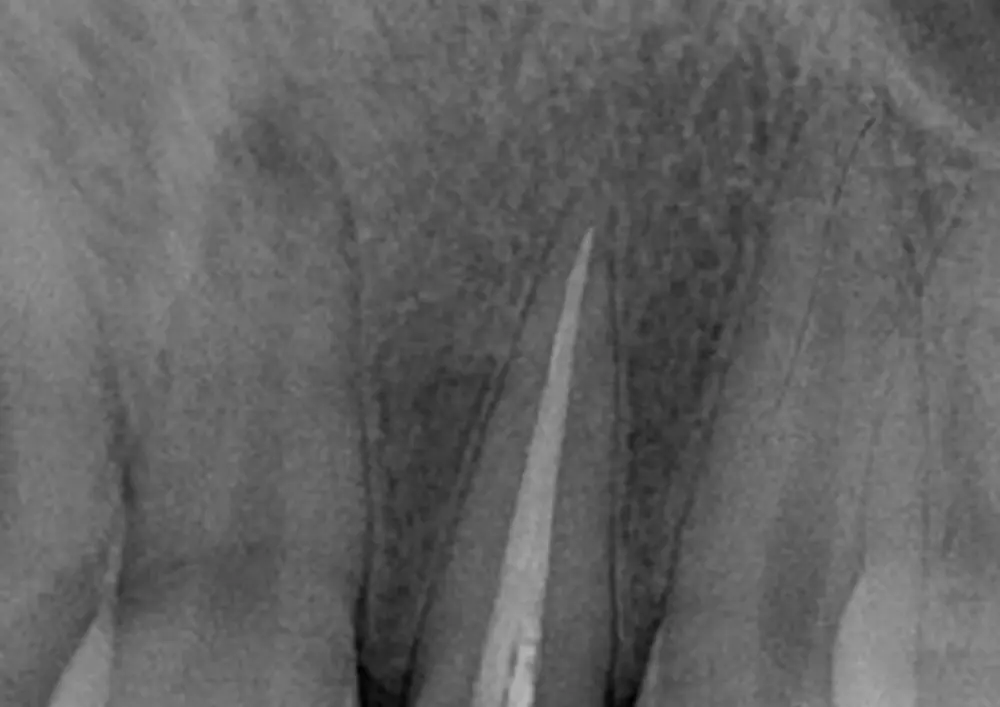

Ekstruzja ortodontyczna vs leczenie chirurgiczne

Ekstruzja ortodontyczna wykorzystywana jest podczas zespołowego leczenia uszkodzeń zębów przebiegających z poddziąsłowym poprzecznym złamaniem korzeni. Stanowi także rozwiązanie w przypadku uszkodzeń typu próchnicowego czy resorpcyjnego. Jest alternatywą dla znacznie ograniczającego estetycznie leczenia chirurgicznego. Lek. stom. Piotr Błasiński w swoim artykule podaje etapy ekstruzji. Zamieszcza także opis przypadku jej wykonania u 15-letniego pacjenta.